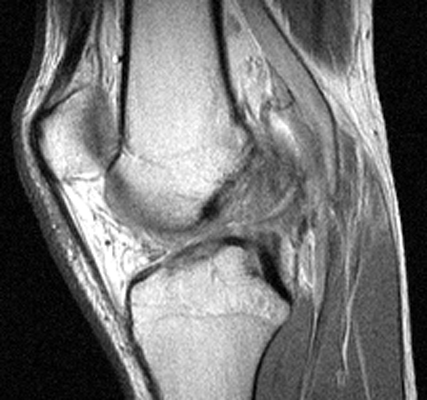

Sagittal T2 weighted and proton density images which reveal complete tear of the ACL with mild increase in marrow signal in the adjacent osseous structures. The bone bruises, as evidenced by increased signal within the marrow, is likely caused by anterior subluxation of the tibia at the time of tear of the ACL accompanied by impaction of the middle portion of the lateral femoral condyle against the posterior portion of the lateral tibial plateau. Signal intensity abnormalities are probably secondary to edema, hemorrhage, and microfracture.